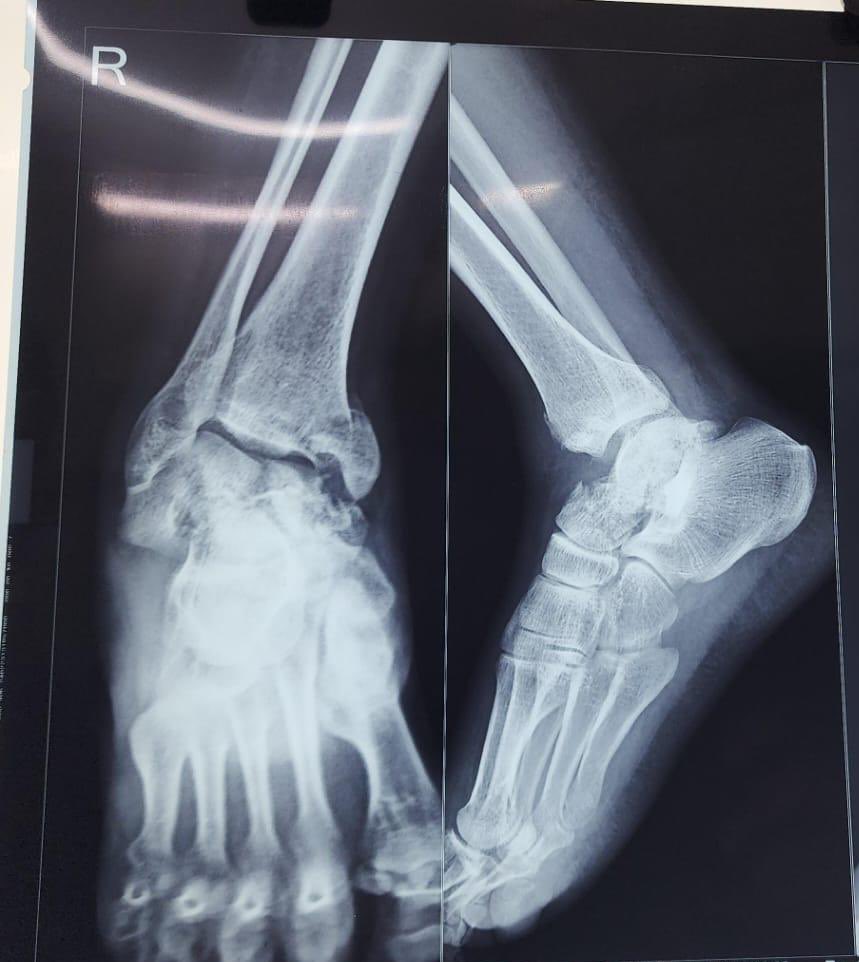

Closed Reduction, Application of Long Leg Cast for Closed Comminuted Diaphyseal Fracture (Middle Third) of the Right Tibia (25/F, Motorcycle accident)

Antonio Tanchuling Jr. M.D. tweet mediaAntonio Tanchuling Jr. M.D. tweet mediaAntonio Tanchuling Jr. M.D. tweet media

@binayamishra16 @BoneJointDoctor @Drlyndonmason Horrible fracture…after applying an ankle-spanning external fixator (span) could repeat the CT to try to fix the medial maleollus, the articular main fragments and the talar neck….for asking…if not possible arthrodesis will be a good option. Good luck, thank you for sharing